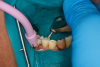

Fig 35. Injection filling of cavity preparation with dual-cure bulk-fill flowable composite to a slight overfill.

Figure 35

Fig 36. Injection overfill smoothed with a brush. At this step, it is important not to disturb the margins.

Figure 36

A deep distal occlusal preparation was performed and a matrix band (Paraband, Practicon) was placed again, such that no wedge needed to be placed (Figure 32). The Groman Etchmaster was utilized to remove biofilm as previously shown in Figure 12. A total etch technique with 37% phosphoric acid was employed (Figure 33), and after thorough rinse and damp dry, a universal adhesive (Scotchbond Universal, 3M) with MDP was applied and light-cured 40 seconds at 1,200 mw/cm2 due to the depth of the box form (Fig- ure 34). Figure 35 shows the dual-cure bulk-fill flowable composite (Bulk EZ Plus, Zest Dental Solutions) being injected into the deep box with a 20-gauge bendable needle. It is important to keep extrusion pressure on the plunger while withdrawing the needle to prevent bubbles or voids in the composite interface with the tooth structure. Overfilling by approximately 10% and smoothing the surface only with brushes promotes good marginal seal (Fig- ure 36). It is critical to not disturb the occlusal surface of any dual-cure bulk-fill flowable with an attempt to "soft sculpt," as that may create marginal voids.